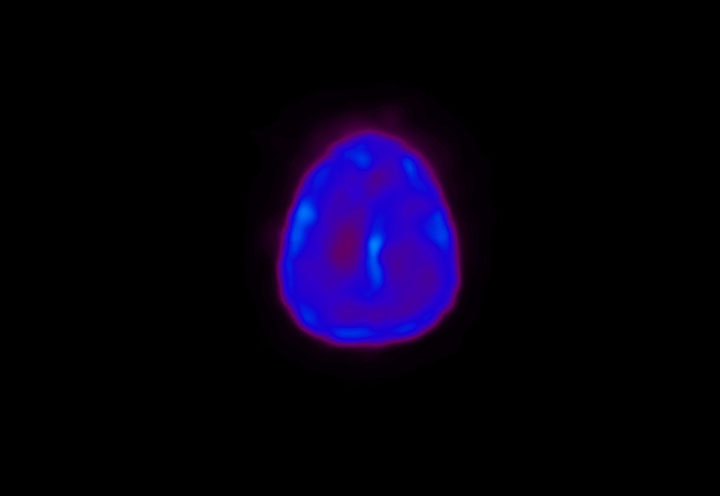

Head / Case4 : Amyloid

Sagittal

Courtesy : Kindai University Hospital

- Injected dose: 3.21 MBq/kg, 18F-Flutemetamol

- Uptake time: 100 minutes

- Scan time: 20 minutes